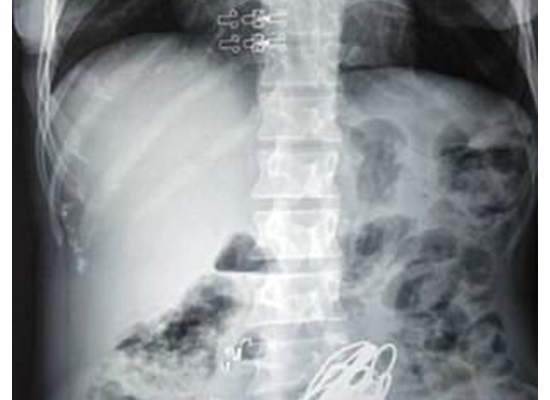

وكشفت صور الأشعة السينية وجود دبابيس الشعر وحلقات النحاس وأجزاء معدنية، داخل بطن المريضة، التي عرفت عن نفسها باسم "سانغيتا".

وقال الدكتور الجراح، نيتين بارمار، الذي أجرى العملية: "أصبحت معدة المرأة صلبة. وكشفت الأشعة السينية عن كتلة كبيرة في معدتها، بينما برزت بعض الدبابيس من رئتها، كما تسبب أحدها في ثقب جدار المعدة، ما دفعنا إلى إجراء العملية على الفور"